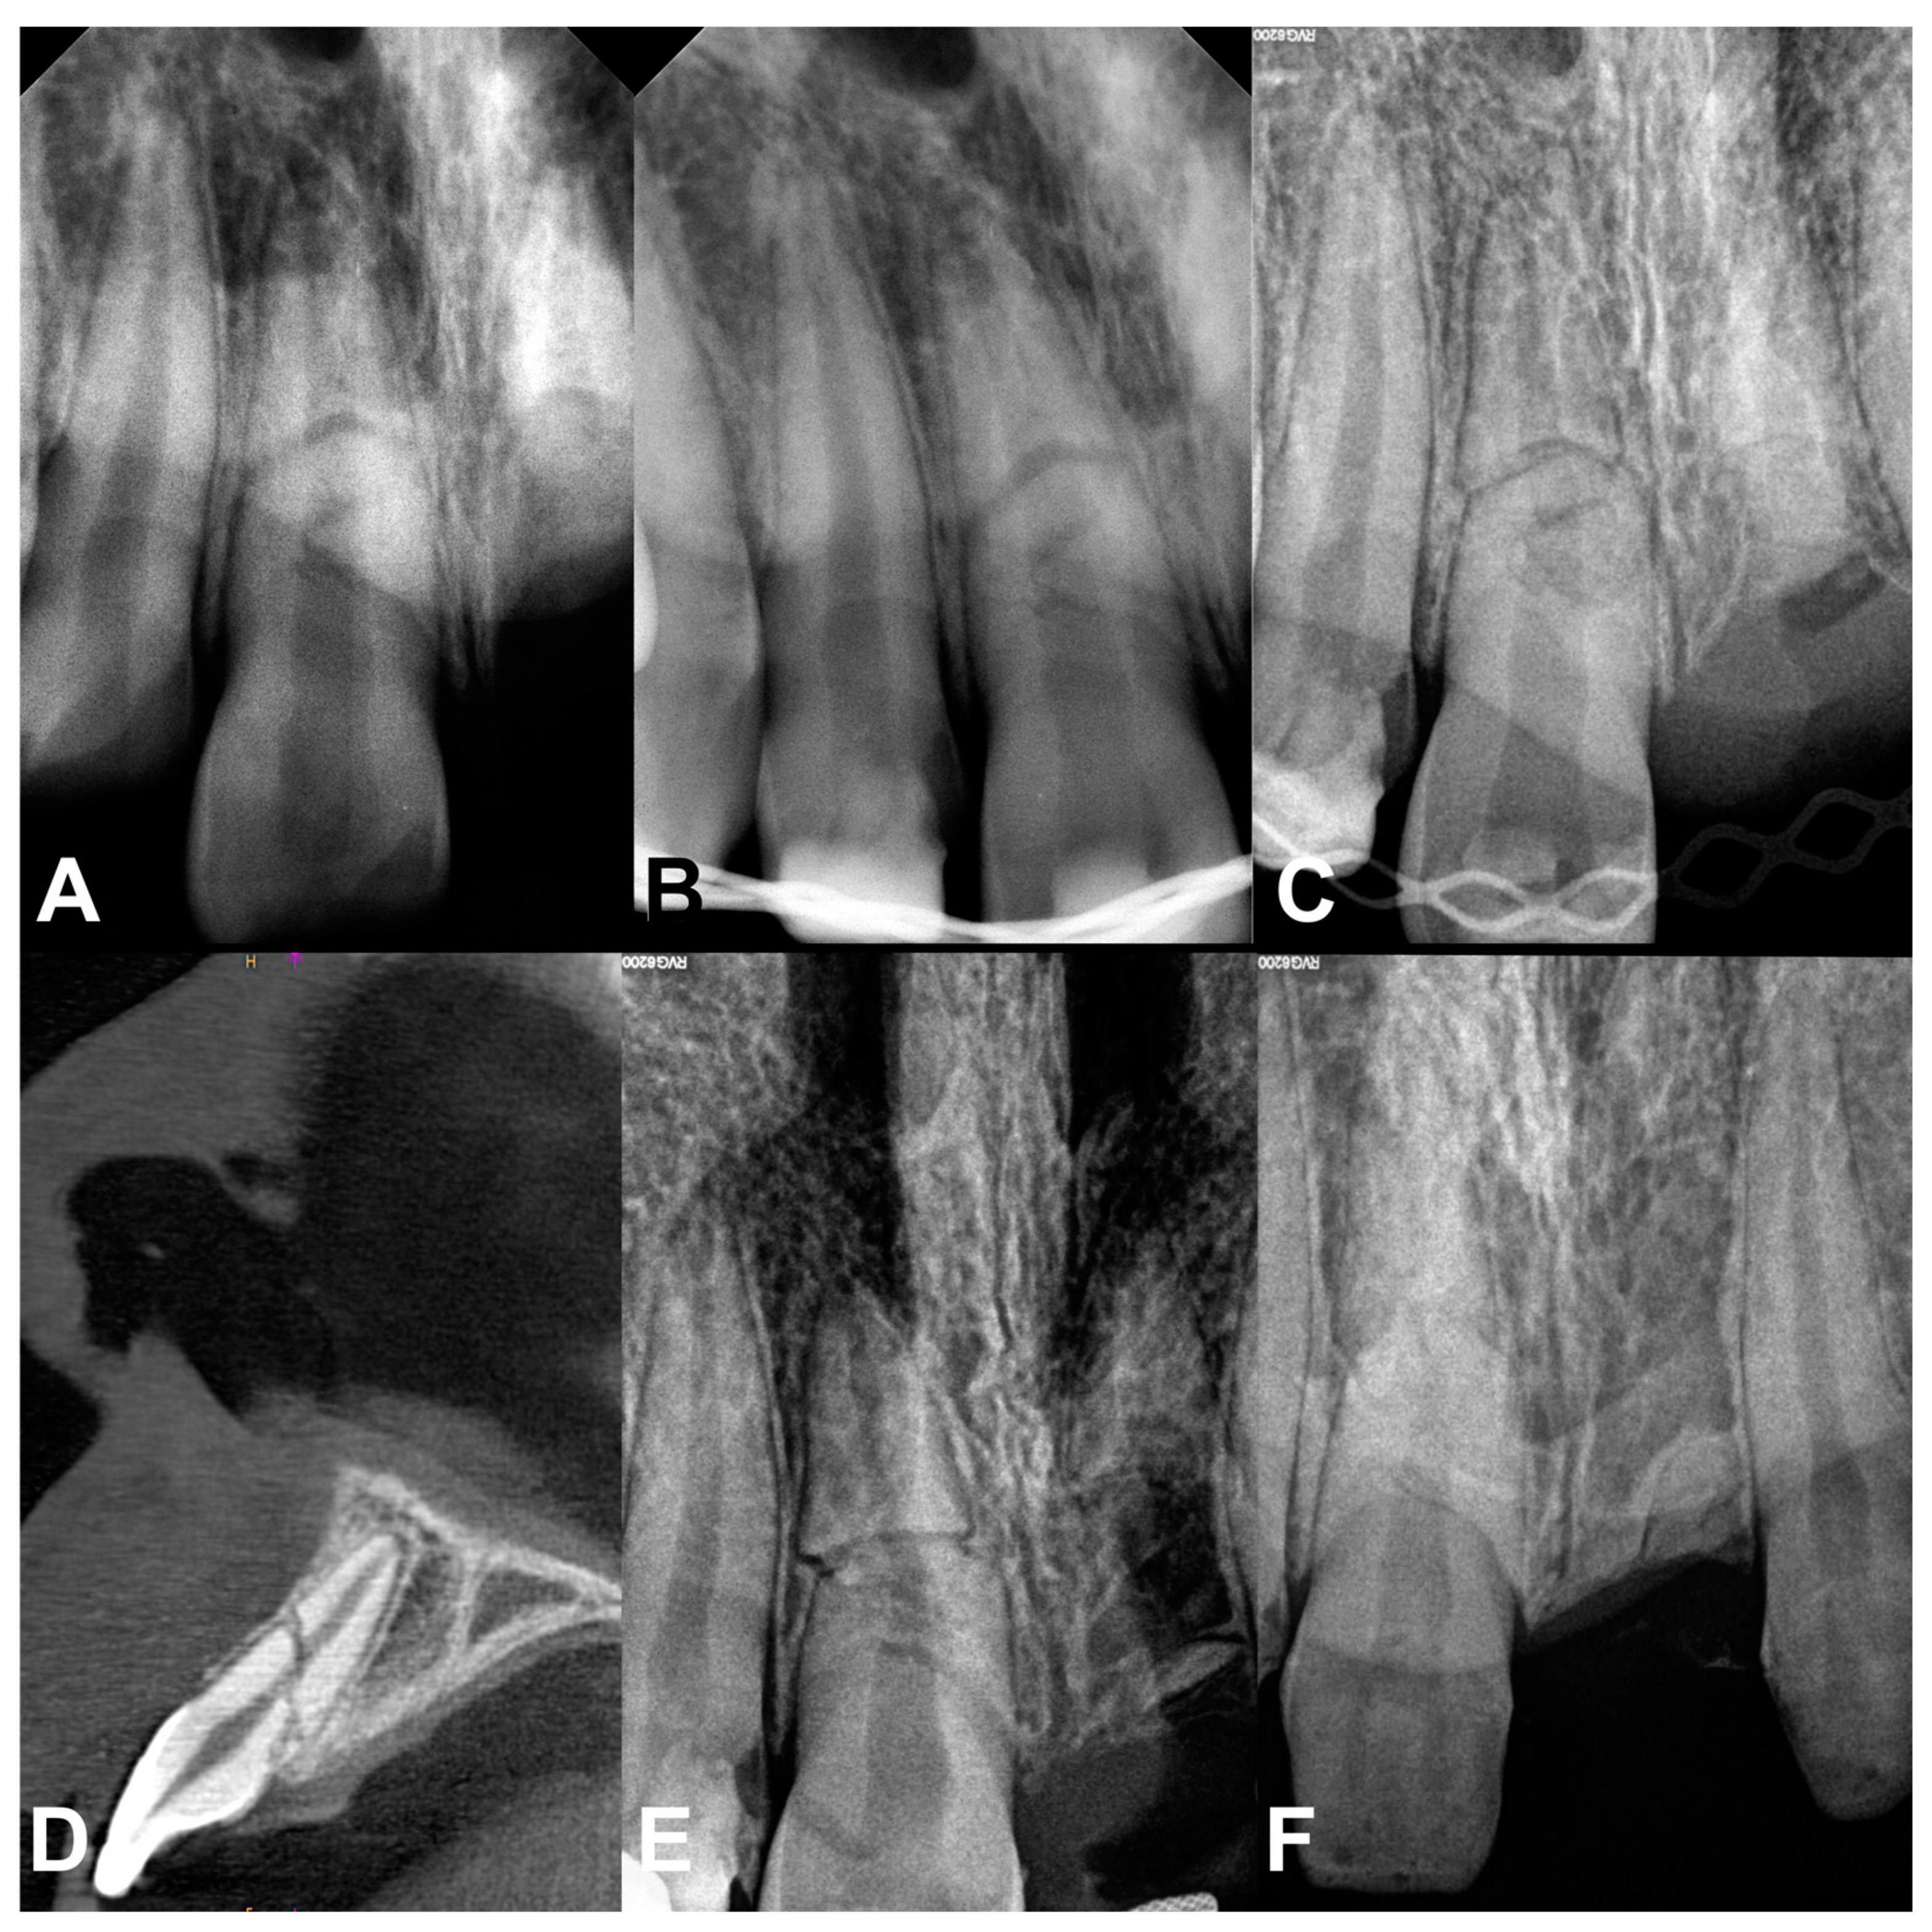

2.1. Case Report 1